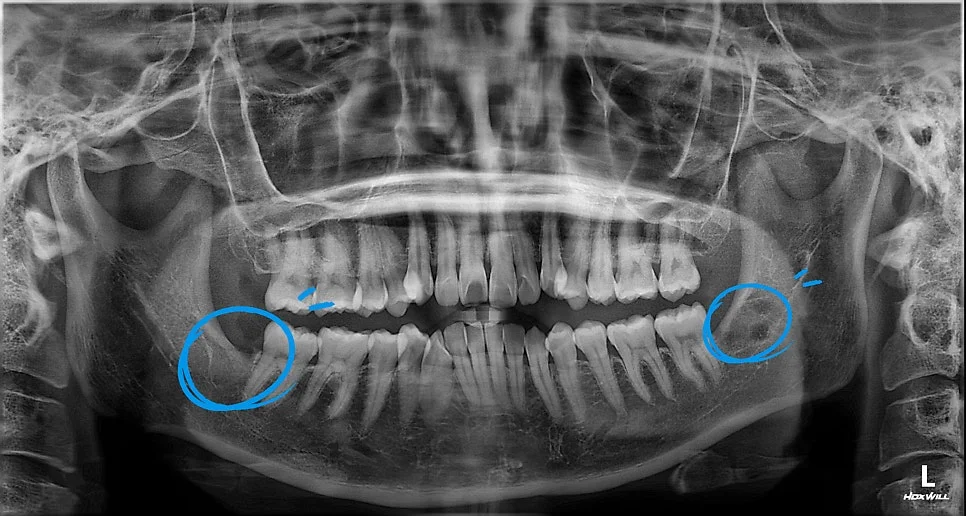

발치 후 파노라마 — 양쪽 사랑니 안전하게 제거, 제2대구치 보존 확인

발치가 끝나고 찍은 파노라마 사진입니다. 좌우 사랑니가 모두 안전하게 제거된 게 보이시죠? 환자분이 제일 걱정하셨던 제2대구치도 무사히 지켜냈습니다.

마지막으로 발치 후 치근단 사진을 확인해 봤습니다. 잔뿌리 하나도 남지 않고 깔끔하게 발치가 잘 된 걸 확인할 수 있죠^^

이런 사진은 수술이 잘 끝났는지 확인하는 중요한 근거가 됩니다~